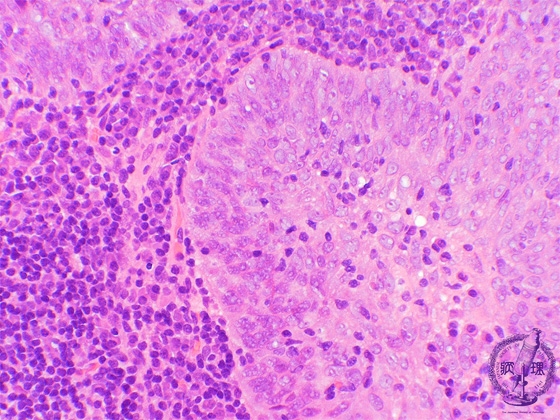

- ★(4)Nasopharyngeal carcinoma (lymphoepithelioma)

e tumor cells in this example show better differentiation as compared to the tumor cells in undifferentiated carcinoma. The tumor cells are invasive, show sheet-like proliferation and form large alveolar lesions (asterisk). Central nucleoli are not prominent and show similar features of squamous cell carcinoma.